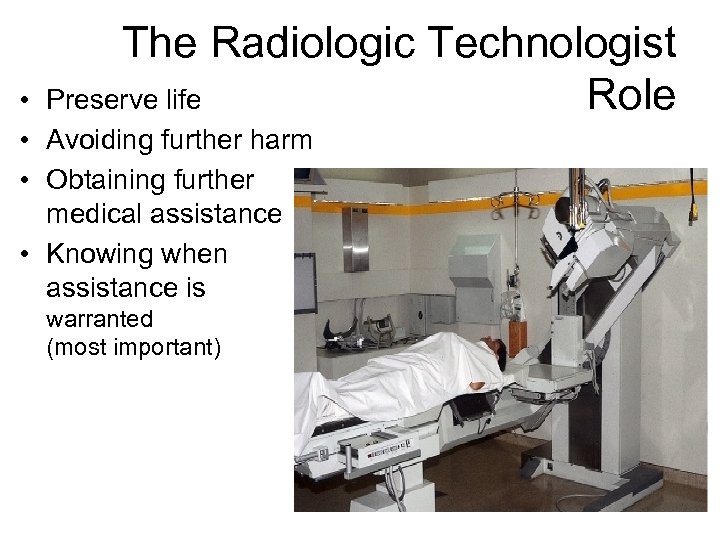

The Radiologic Technologist Preserve life Role • • Avoiding further harm • Obtaining further medical assistance • Knowing when assistance is warranted (most important)

The Radiologic Technologist Preserve life Role • • Avoiding further harm • Obtaining further medical assistance • Knowing when assistance is warranted (most important)